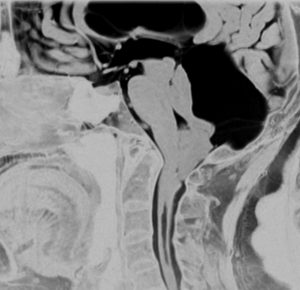

テント下くも膜のう胞

高齢の女性のくも膜のう胞です。テント下,上小脳槽にある大きなくも膜のう胞です。小脳扁桃ヘルニアになり,脊髄空洞症を併発しています。第4脳室出口の閉塞で水頭症となっていました。症状は数年かかって徐々に進行した歩行障害で,転倒しやすくなったとの主訴で受診しました。これは,のう胞壁を開頭手術で摘出する必要があるものです。数十年もある大きなのう胞ですから,意外に周囲の脳槽は狭いものです。実際に顕微鏡手術で,迂回槽と交通をつけるようにのう胞壁を除去したのですが,髄液交通を確保するのはとても難しいものでした。内視鏡ではリスクが高いかもしれません。